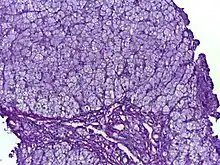

![]() | |

| Glycogen storage disease in hepatocytes | |